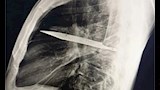

في واقعة طبية نادرة، اكتشف أطباء في تنزانيا شفرة سكين معدنية كبيرة مستقرة داخل تجويف صدر رجل يبلغ من العمر 44 عاما، بعد مرور ثماني سنوات على تعرضه لطعنات متكررة دون أن يعلم ببقاء الشفرة في جسده.

وأظهرت الفحوص السريرية أن الجزء الأيمن من صدره لا يتمدد بالكامل أثناء التنفس، فيما كشفت الأشعة السينية وجود شفرة سكين كبيرة عالقة في تجويف الصدر، ممتدة من الظهر إلى مقدمة القفص الصدري، ومحاطة بطبقات من القيح والأنسجة الميتة.